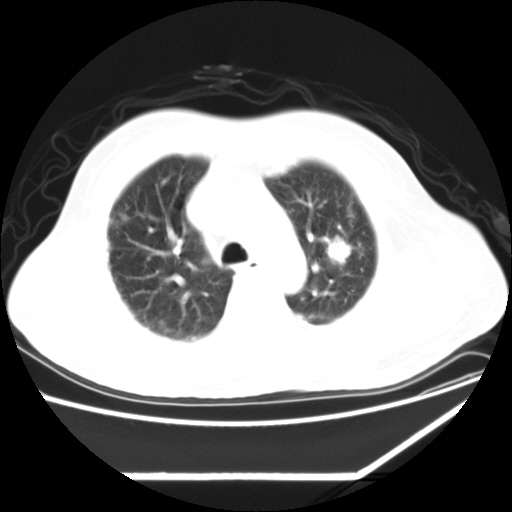

男,57,畏寒,发热

双肺多发结节样病灶,部分内见透光区,纵隔内见淋巴结肿大。结核临床如有畏寒,高热,白细胞增高首先考虑迁徙性肺脓肿(多是金黄色葡萄球菌感染)。

注意除外转移瘤。

双肺典型的亚急性粟粒性肺结核

双侧胸膜结核